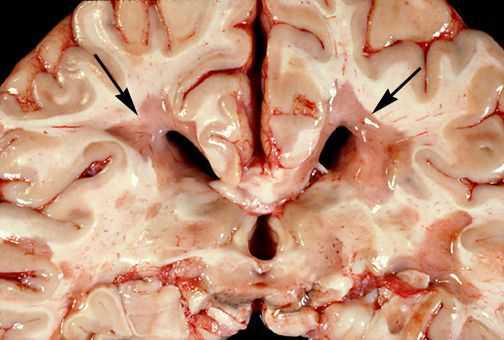

Для того, чтобы понять механизм развития РС, необходимо ознакомиться с патологической анатомией данного заболевания.

При микроскопическом исследовании обнаруживаются заметные и достаточно характерные изменения, выявляемые с наибольшим постоянством в спинном мозгу, мозговом стволе и полушариях головного мозга. Видны множественные бляшки различной величины (от точечных до весьма массивных, которые, к примеру, занимают весь поперечник спинного мозга), рассеянные преимущественно в белом веществе. Такая множественность и разбросанность очаговых изменений и определяет название болезни.

![Очаговые изменения в белом веществе мозга]()

Отдельные бляшки имеют округлую форму, они нередко сливаются и создают изменения сложных очертаний. Цвет бляшек на разрезе розовато-серый (недавно образовавшиеся очаги) или серый, желтоватый (старые очаги).

![Образовавшиеся бляшки]()

При разрезе бляшки определяется их большая плотность по сравлению с нормальной мозговой тканью. Эти уплотнения, склерозирование бляшек дало возможность охарактеризовать заболевание как склероз.